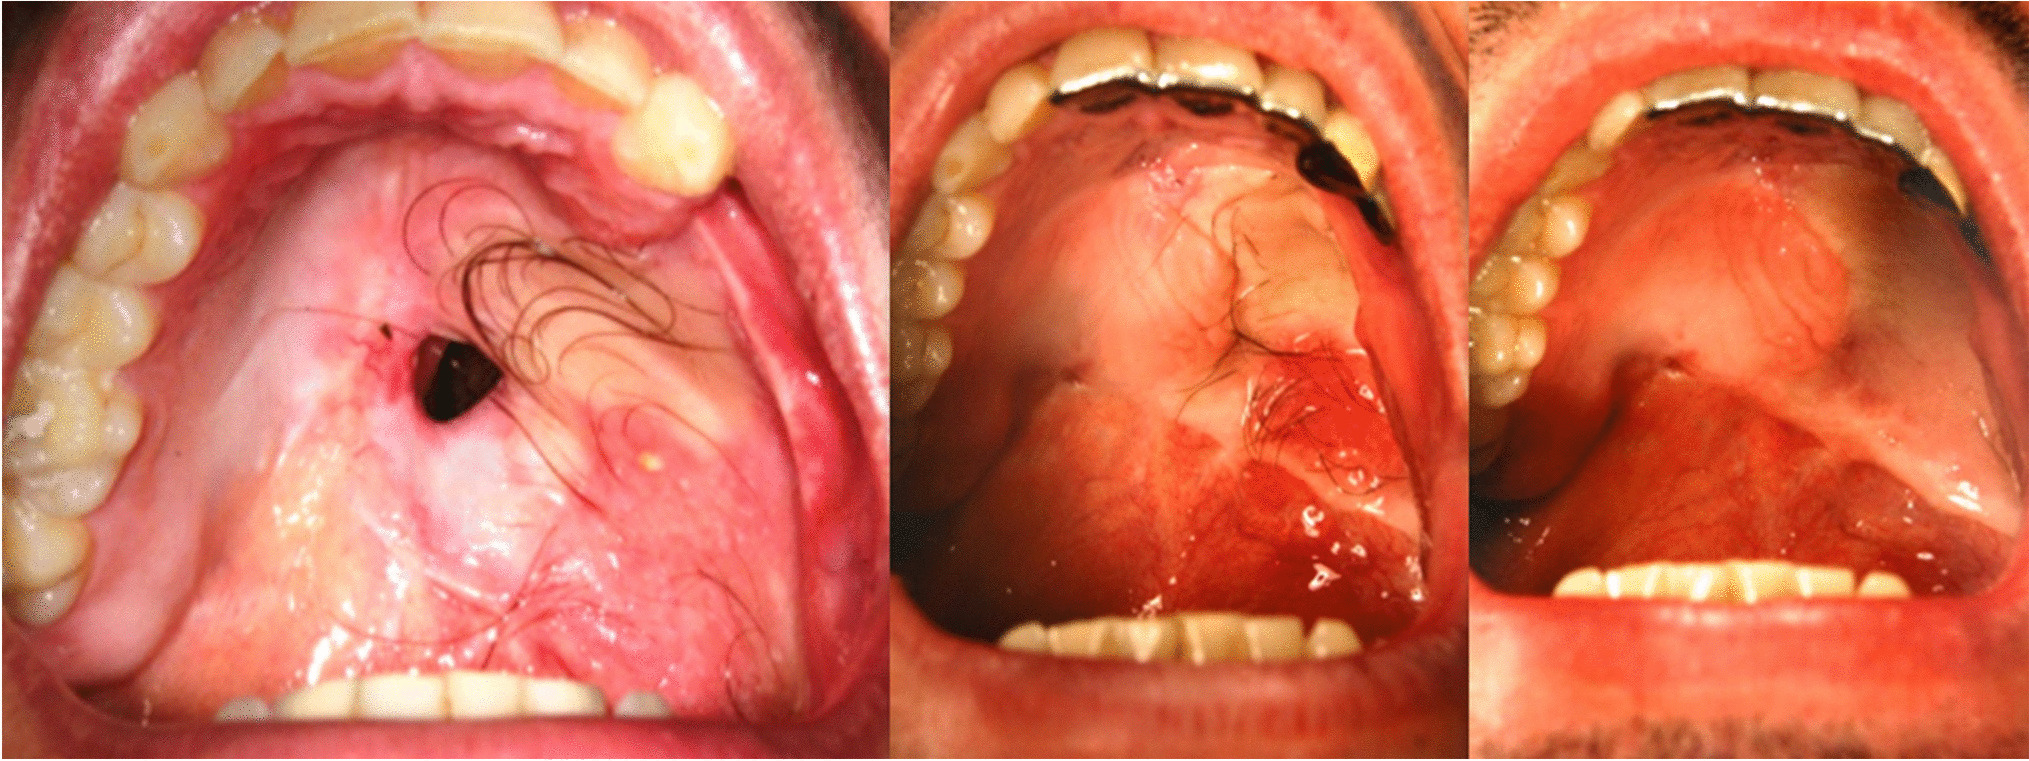

We present a series of six male patients aged between 41 and 75 years, who underwent successful treatment of intraoral hair using a long-pulsed alexandrite laser. Following surgical resection of oral malignancy, our patients developed hairy mouth from the use of soft tissue flaps obtained from hair-bearing skin for primary reconstruction. Prior to laser treatment, they had not received any other depilation therapy. The patients required 3–7 sessions of treatment with the long-pulsed alexandrite laser (Quantas Duetto or Cynosure Elite) performed with or without cooling. Fluence ranged between 16 and 30 J/cm2 with a pulse duration between 14 and 40 ms. The spot size was 12–14 mm, and treatment intervals were 4–6 weeks. Following laser treatment, all six patients achieved excellent results with full suppression or a good reduction in hair growth (Fig. 1). Treatment was well-tolerated with no complications and there was no difference in perceived discomfort with or without dynamic cooling. One operator limitation we observed was some technical difficulty in accessing the back of the mouth.

Fig. 1

Left to right: clinical imaging showing the progressive reduction of intraoral hair postlaser treatment. Please note that defect was repaired by the maxillofacial surgery department during the early course of the treatment